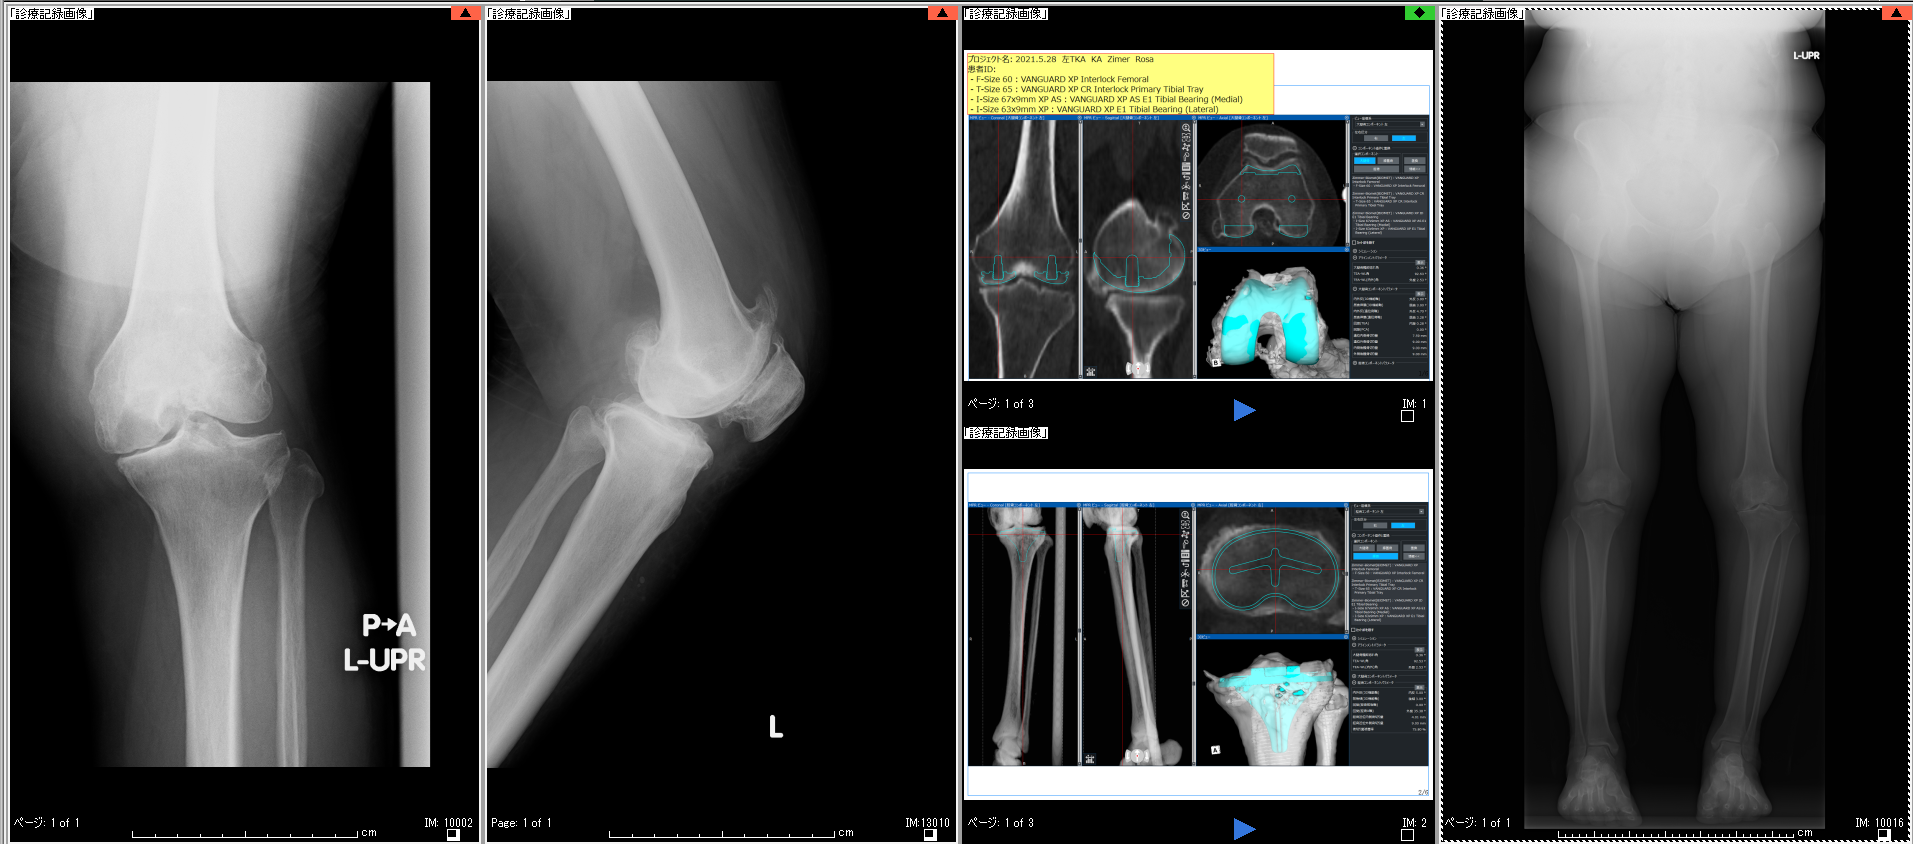

最近の人工関節テクノロジーの進歩は目覚ましく、インプラントの耐久性が格段に向上しており、人工関節の耐用年数は20年~30年といわれています。この長期の耐久性を保つためには正確な手術が重要であり、当センターではコンピューター・シミュレーションによる術前計画を行った上で、最先端手術支援ロボットを導入して多くの手術を行っています(現段階では膝、7月から股関節も一部)。